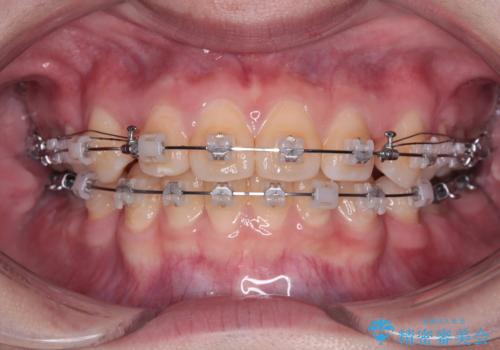

- 矯正装置

- クリアブラケット

- 転勤により東京へ移られることになり転院先を探されていた患者様です。ワイヤー矯正の途中での急な転勤なうえ、今後2~3年以内に再度転勤になる可能性もあるというご事情でした。

そのため、限られた期間内に効率よく治療を完了するために、「抜歯スペースの確実な閉鎖」「深い噛み合わせ(過蓋咬合)の改善」の2点を主軸とした治療計画を立てました。

結果的に1年半で、再度転勤になる前に治療を終えることができました。